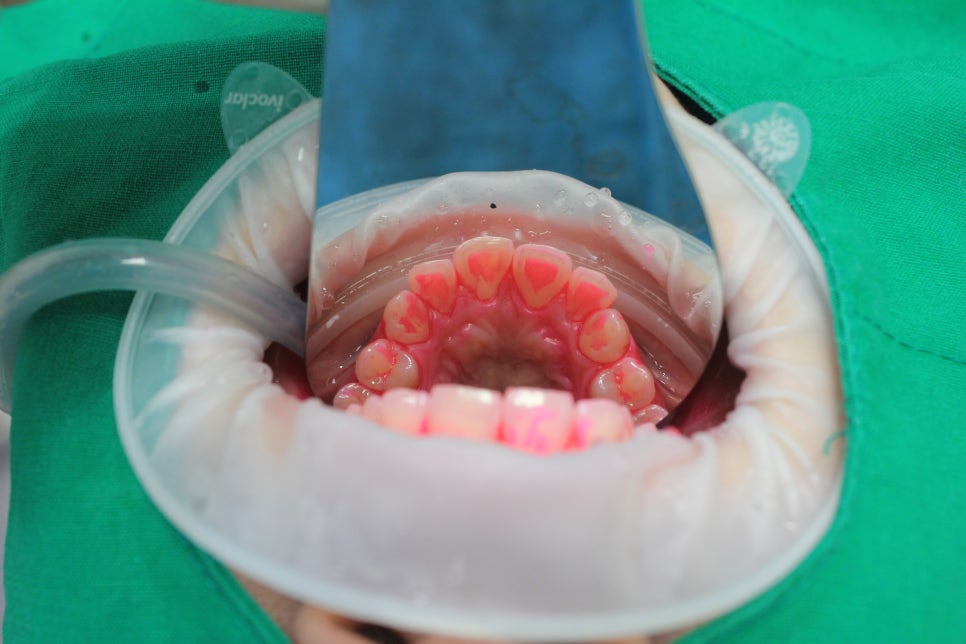

종로 30분 치과 치아 파우더 클리닝 전문가 치아 미백 케이스 본문

덴트데일리 전문가 미백 프로그램으로 환하게 변신한 20대 고객님 사례

오늘은 덴트데일리에서 전문가 미백 프로그램을 통해 눈부신 변화를 경험한 20대 고객님의 이야기를 소개해 드릴게요! 😊

2M 3에서 1M 1까지, 환해진 치아 톤!

첫 내원 시 고객님의 치아 밝기는 2M 3였는데요, 덴트데일리의 파우더 클리닝과 전문가 미백 프로그램을 진행한 후 1M 1까지 톤업! 치아 미백을 고려할 때, 단순히 색상만 밝아지는 것이 아니라 건강한 미소를 유지하는 것도 중요하죠. 덴트데일리는 치아를 더 환하게 만드는 동시에 구강 건강까지 모두 챙길 수 있도록 체계적인 관리 시스템을 제공하고 있어요.

파우더 클리닝으로 미백효과 극대

미백 효과를 극대화하기 위해 고객님께서는 먼저 물과 에리트리톨을 이용한 파우더 클리닝을 받으셨습니다. 이 과정에서는 치아 표면에 붙어 있는 바이오필름과 세균을 말끔하게 제거해, 미백 효과를 더욱 높일 수 있었어요! 파우더 클리닝은 단순한 치아 세정이 아닌 구강 곳곳에 있는 세균막들을 제거하여 구강 건강 개선에도 큰 도움을 주는 중요한 과정이에요. 잇몸 건강을 지키면서 미백 효과까지 극대화할 수 있는 덴트데일리만의 특별한 서비스랍니다. 💡